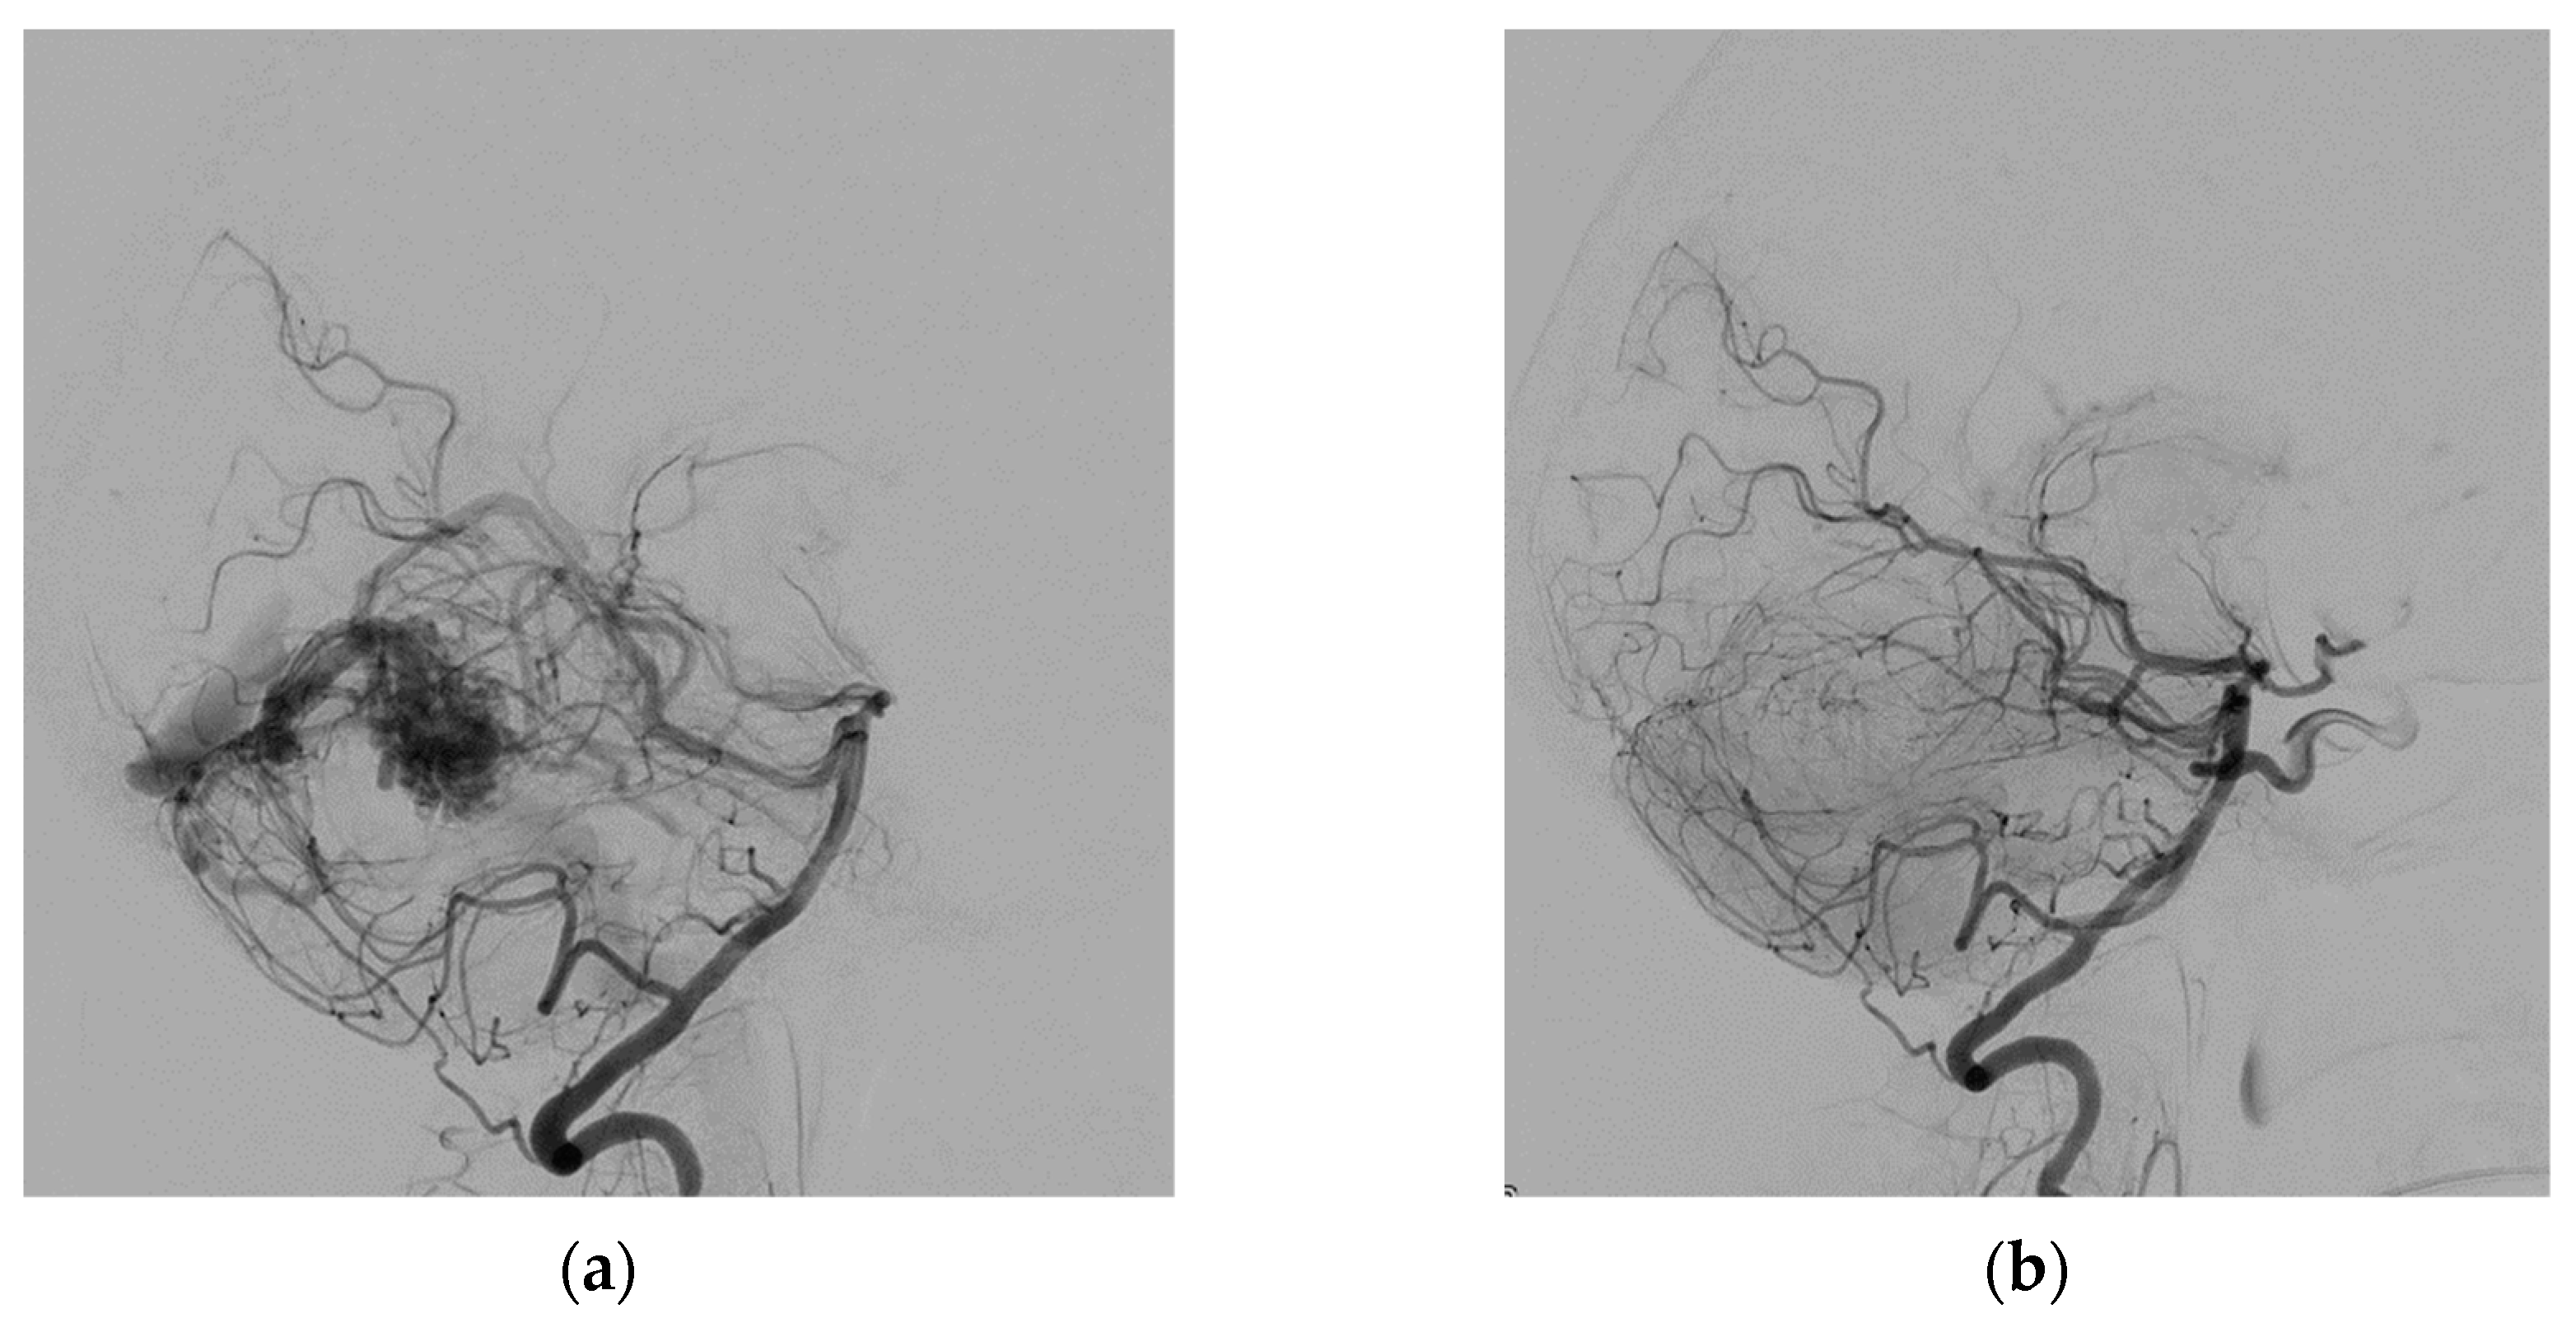

- Zeleňák, K.; Sýkora, J.; Vorčák, M.; Zeleňáková, J.; Kurča, E.; Deriggo, J.; Hanko, M.; Kolarovszki, B. Transvenous embolization of a ruptured brain arteriovenous malformation. Cesk. Slov. Neurol. N. 2020, 83, 441–443. [Google Scholar] [CrossRef]